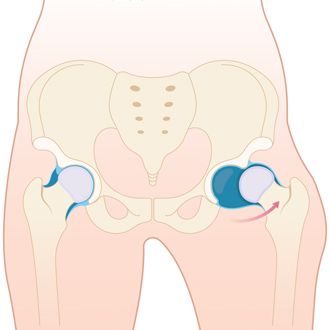

Вывих бедра (Hip dislocation) — это состояние, при котором головка бедренной кости выходит из вертлужной впадины тазовой кости [1].

Тазобедренный сустав очень прочный и стабильный, поэтому вывихнуть его можно лишь в чрезвычайных ситуациях или при определённых заболеваниях, которые поражают костные структуры сустава.